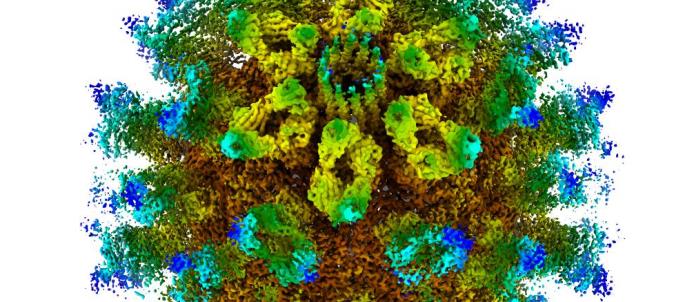

£250K grant to fund ‘game-changing’ immunotherapy research for prostate cancer